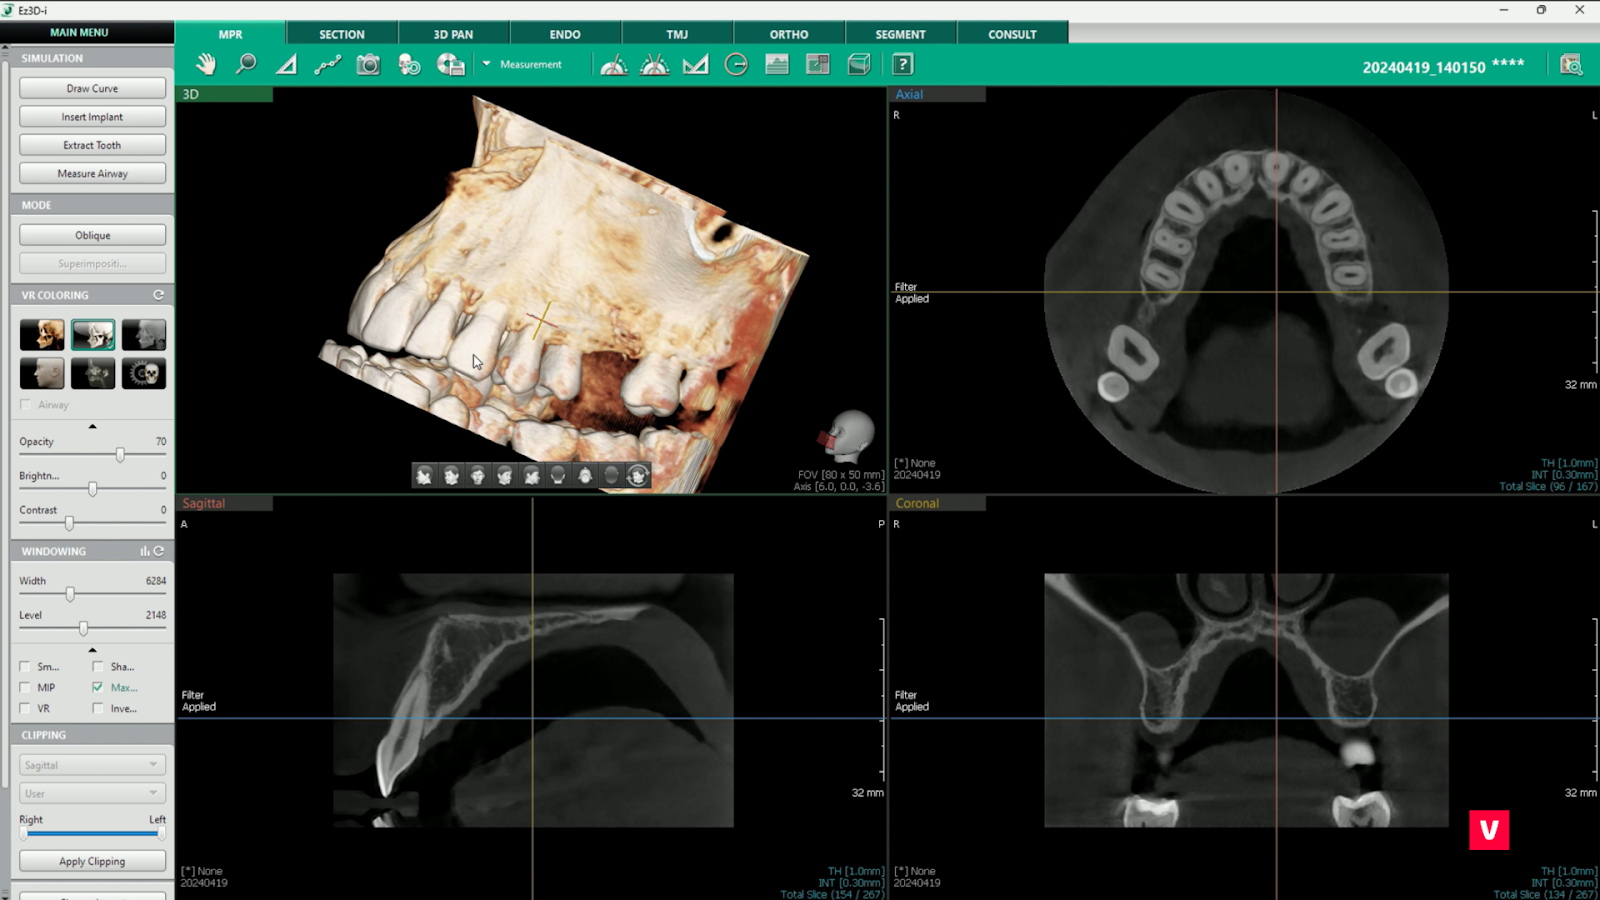

Computerul tomograf cu fascicul conic este o tehnologie de ultimă generaţie în domeniul imagisticii ce permite vizualizarea în plan tridimensional a zonelor scanate. Pentru vizualizarea tomografiei, pe lângă analiza efectuată de către medicul specialist, se folosește un software performant cu ajutorul căruia imaginile pot fi manipulate pentru a arăta diverse unghiuri, pot măsura adâncimi, grosimi, densităţi, pot selecta numai anumite ţesuturi etc.

Pentru a înțelege cum poate CBCT să îmbunătățească procesul de lucru, analizăm studiul de caz al unui pacient care a ajuns în cabinetul medical cu durere persistentă la dintele 11. Imaginea OPG nu a arătat nicio problemă cu rădăcina dintelui. Medicul dentist care s-a ocupat de caz a decis însă să scaneze pacientul și cu aparatul CBCT, pentru o evaluare mai amănunțită. Imaginea 3D i-a confirmat suspiciunile și anume faptul că rădăcina dintelui 11 era fracturată.

Folosirea imagisticii CBCT a scurtat enorm soluționarea problemei și i-a oferit medicului timp suplimentar pentru tratamentul pacientului.